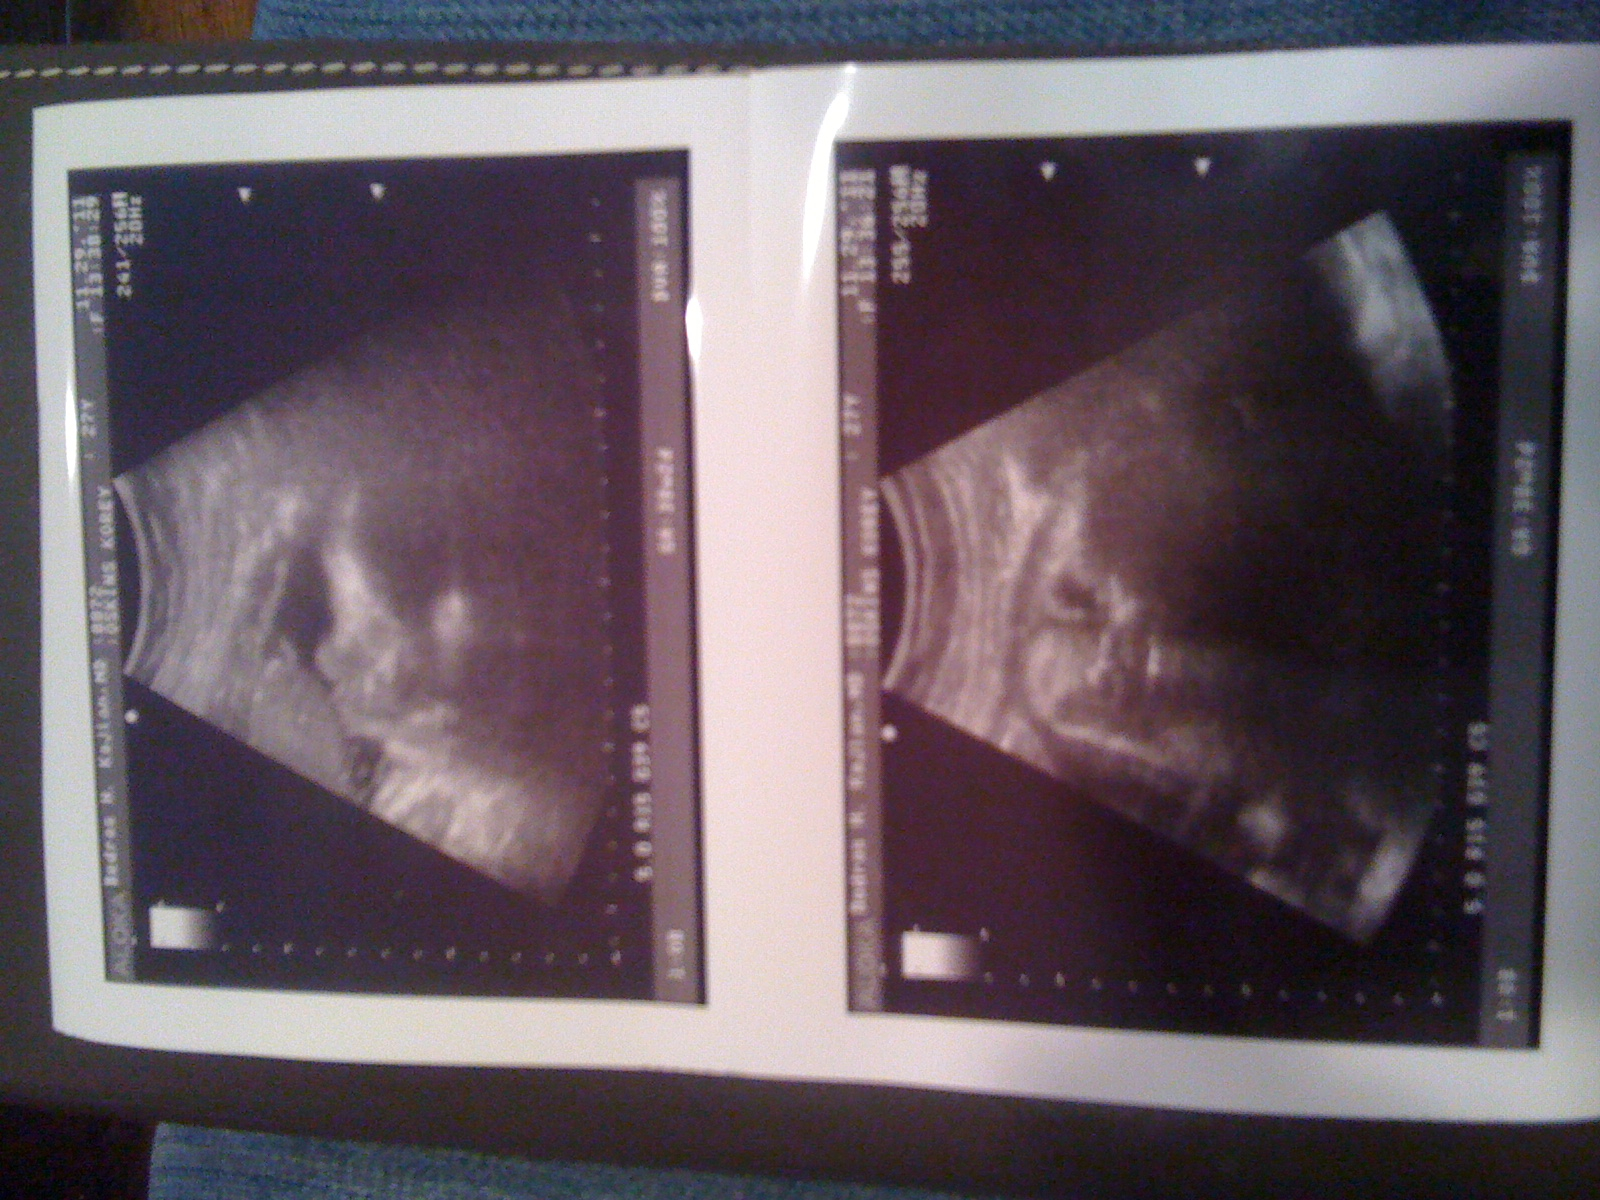

Three pictures for you today: me at 38 weeks, side and front, and two ultrasound pictures of the baby.

The top picture is his side facial profile (you can see his nose and lips on top) and the bottom picture has him staring right at you with his eyes on the right.